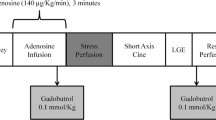

CMR Examination

All CMR studies were performed with a 1.5T magnetic resonance system (Signa Excite®, GE Medical Systems, Milwaukee, USA) using an 8-element phased array surface coil (Cardiac coil, GE Medical Systems). Left ventricular (LV) parameters were measured using long-axis (two-chamber and four-chamber-views) functional steady-state free precession (SSFP) sequence images as part of our clinical routine protocol. After infusion of adenosine at a constant rate of 140 μg/kg per minute over three minutes (Spectris MR injector, Medrad, Indianola, USA) first-pass kinetic of a gadolinium-based contrast agent (Omniscan®, GE Healthcare Buchler, Germany; 0.1 mmol/kg) was measured in 4 contiguous short axis orientations at every heart beat using a hybrid gradient echo/echo-planar pulse sequence (echo time 1.2 ms, flip angle 25°, slice thickness 8 mm, field of view 32–34 × 24–25.5 cm, matrix 128 × 96) as previously described [7, 20]. Echo time was reduced to 1.2 ms for reducing susceptibility artifact as sometimes seen in gradient echo sequences [21]. Ten minutes after stress perfusion a second perfusion study with the same orientation and with the same setting was performed at rest without adenosine infusion. Ten minutes after this second bolus, LGE images were acquired by using an inversion-recovery prepared gated fast-gradient echo-pulse sequence (repetition time 6.7 ms; echo time 3.3 ms; flip 20°; inversion time individually adjusted; slice thickness 8 mm; rectangular field of view 30 to 34 cm; matrix 256 × 160). Again, three long axes, 4–5 short axes as planned in the perfusion study as well as contiguous short axes views using a 3D 20 slice sequence were acquired.